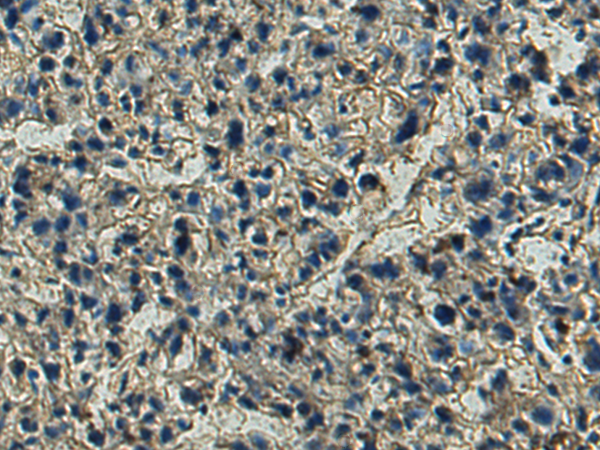

分类: 科研抗体货号: P05302别名:应用: IHC反应种属: Human